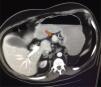

Ingresó en el servicio de digestivo el 07-10-2011 hasta el 20-11-2011 por cuadro de dolor abdominal inespecífico. Durante el ingreso presentó vómitos alimenticios a repetición, pruebas posteriores arrojan la presencia de pancreatitis crónica, iniciando tratamiento enzimático por parte de digestivo con leve mejoría clínica. Continua con dolor digestivo, cuadro de marcada ansiedad, mucha labilidad emocional dificultando considerablemente el interrogatorio y la exploración física. Cabe destacar que siendo tan inespecífico el cuadro digestivo muchas veces cedía con apoyo psicológico por parte de enfermería, AINE, antieméticos o ansiolíticos. La persistencia de dolor abdominal inespecífico, sobre todo durante sesiones de hemodiálisis hace sospechar de una enfermedad de base que no ha sido aún descubierta. Debido a ello se realiza una ecografía abdominal, sin hallazgos a resaltar, salvo enfermedad renal previa ya conocida. Se solicita una TAC abdominal, donde se observa una dudosa masa de 2cm que protruye en borde superior del cuerpo de páncreas cercano al istmo, así como una hernia de Bochdalek.

El paciente es referido al servicio de cirugía y de endocrinología siendo diagnosticado de un probable tumor neuroendocrino. Como tratamiento se realiza laparotomía exploratoria subcostal, observado una masa muy vascularizada de 2,5cm de diámetro sin contacto aparente con el conducto de Wirsung (fig. 2). Se aprecia estabilidad de la lesión y Ki-67 inferior al 2%, por lo que se decide enucleación del tumor con paciente de alto riesgo, realizándose esta, sin incidencias. El diagnóstico anatomopatológico mostró una masa en el cuerpo del páncreas de 2cm de diámetro, G1 de la clasificación de la OMS de 2010, que respeta el borde quirúrgico, aunque se sitúa a menos de 1mm de este. Cromogranina a isintafisina: (+) Ki-67: bajo índice de proliferación celular (−1%). Ganglio linfático de curvatura mayor, tejido adiposo sin alteraciones histológicas reseñables. Quiste solitario peritoneal. El paciente permaneció estable en el postoperatorio, siendo transferido a planta de medicina interna para su recuperación.